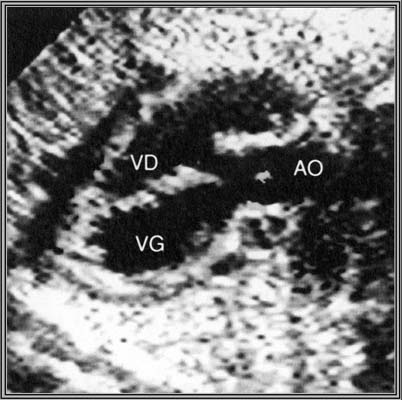

Incidence cinq cavités : Le gros vaisseau chevauche le septum IV et reçoit le sang des deux ventricules.

1.Tétralogie de Fallot

- CIV

- Chevauchement de l’aorte sur le septum IV

- Sténose pulmonaire (dont dépend le pronostic)

- Hypertrophie ventriculaire droite (peut manquer in utero)

- Aorte parfois dilatée

- Valves pulmonaires épaissies à mobilité réduite